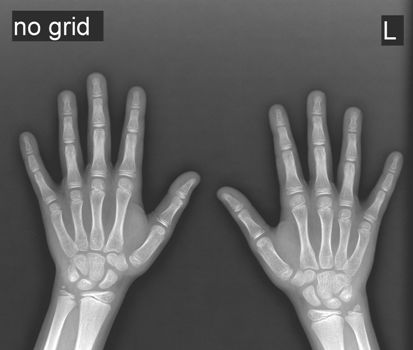

В рентгенологический кабинет, по направлению от детского эндокринолога клиники №1 Витерра Беляево, поступил пациент мужского пола, в возрасте 10 лет, для оценки развития скелета.

Пациенту было проведено исследование - цифровая рентгенография кистей рук в прямой проекции и с режимом NO GRID.

На рентгенограмме кистей - зоны роста и точки окостенения соответствуют 10 (+/- полгода) годам.

Рентгенологический возраст соответствует хронологическому.